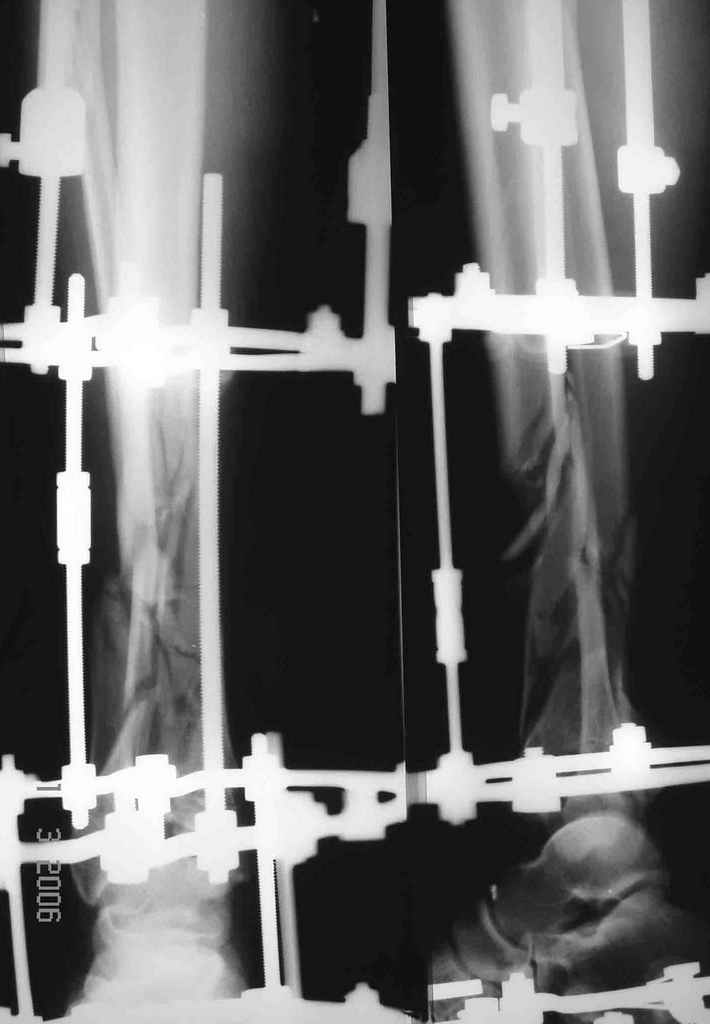

Отправитель: Alexey Smirnov 27 Март 2006, 21:52

Наверно не дошел, вот еще раз.

8.jpg

14KB (14977 bytes)